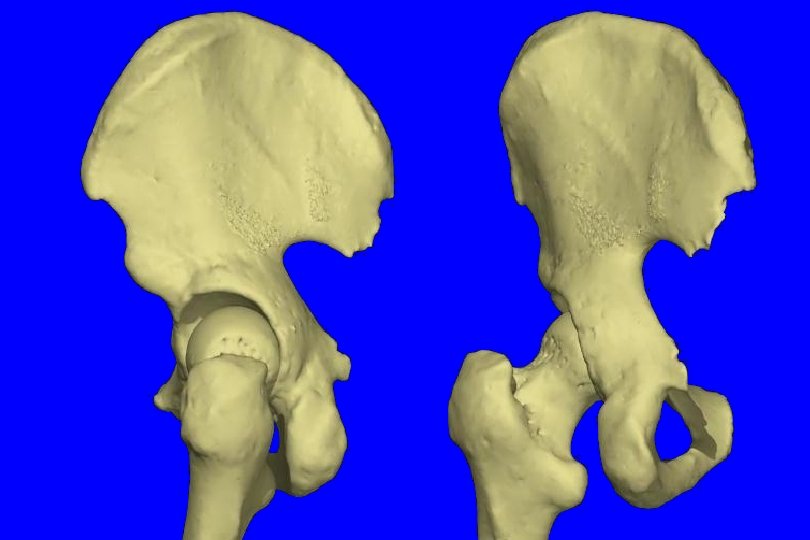

Kemik patolojileri: Asetabulum Asetabular displazi, anteversiyonda artma Ön duvar zayıf, hipoplazik, sığ Femur Koksa valga (KDA artmış) Femur başı anteversiyonu artmış